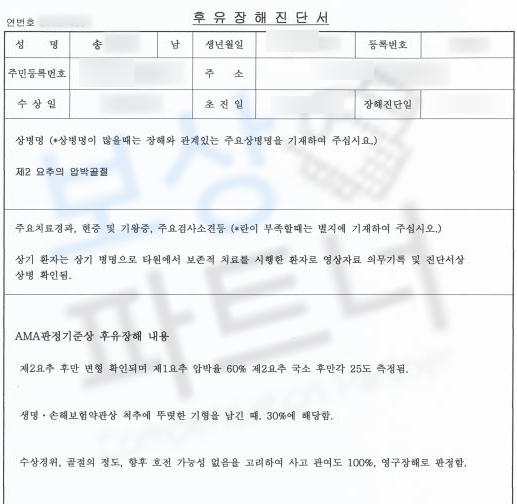

상세불명 부위의 척추의 골절 T08.0

진단을 받으셨꼬 Mri를 찍어보니

요추2번 척추압박골절 확정되었습니다. 주치의는 두달간의 보존치료를 권하였고

가입시기에 따른 약관의 변화와 예상 보상 범위를 말씀드린 후 사건을 수임하여 진행하게 되었는데요, 장해의 잔존을 증명하기 위해서는 의료 전문의의 후유장해 진단서가 필요한데

공신력있는 타 병원의 전문의로부터

AMA 후유장해 진단서 발급을 하게 되었습니다. 이 후 손해사정서도 함께 작성하여 각 보험회사에 청구하였는데요,. 역시나 보험회사에서는 압박률과 후만각의 의료자문을 시행하겠다며 보상파트너와 약 한달간의 분쟁을 하였지만

결국 보상파트너가 처음 청구한

척추에 뚜렷한 기형을 남긴 때 30% 영구장해

인정받게 되어